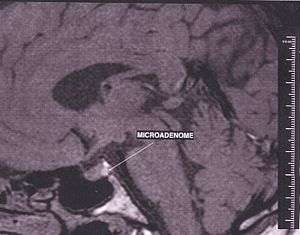

Adenomas which exceed 10 millimetres (0.39 in) in size are defined as macroadenomas, with those smaller than 10 mm referred to as microadenomas. Most pituitary adenomas are microadenomas, and have an estimated prevalence of 16.7% (14.4% in autopsy studies and 22.5% in radiologic studies).[2][3] A majority of pituitary microadenomas often remain undiagnosed and those that are diagnosed are often found as an incidental finding, and are referred to as incidentalomas.

Tumors which cause visual difficulty are likely to be a macroadenoma greater than 10 mm in diameter; tumors less than 10 mm are microadenoma.

The differential diagnosis includes pituitary tuberculoma, especially in developing countries and in immumocompromised patients.[30] The diagnosis is confirmed by testing hormone levels, and by radiographic imaging of the pituitary (for example, by CT scan or MRI).